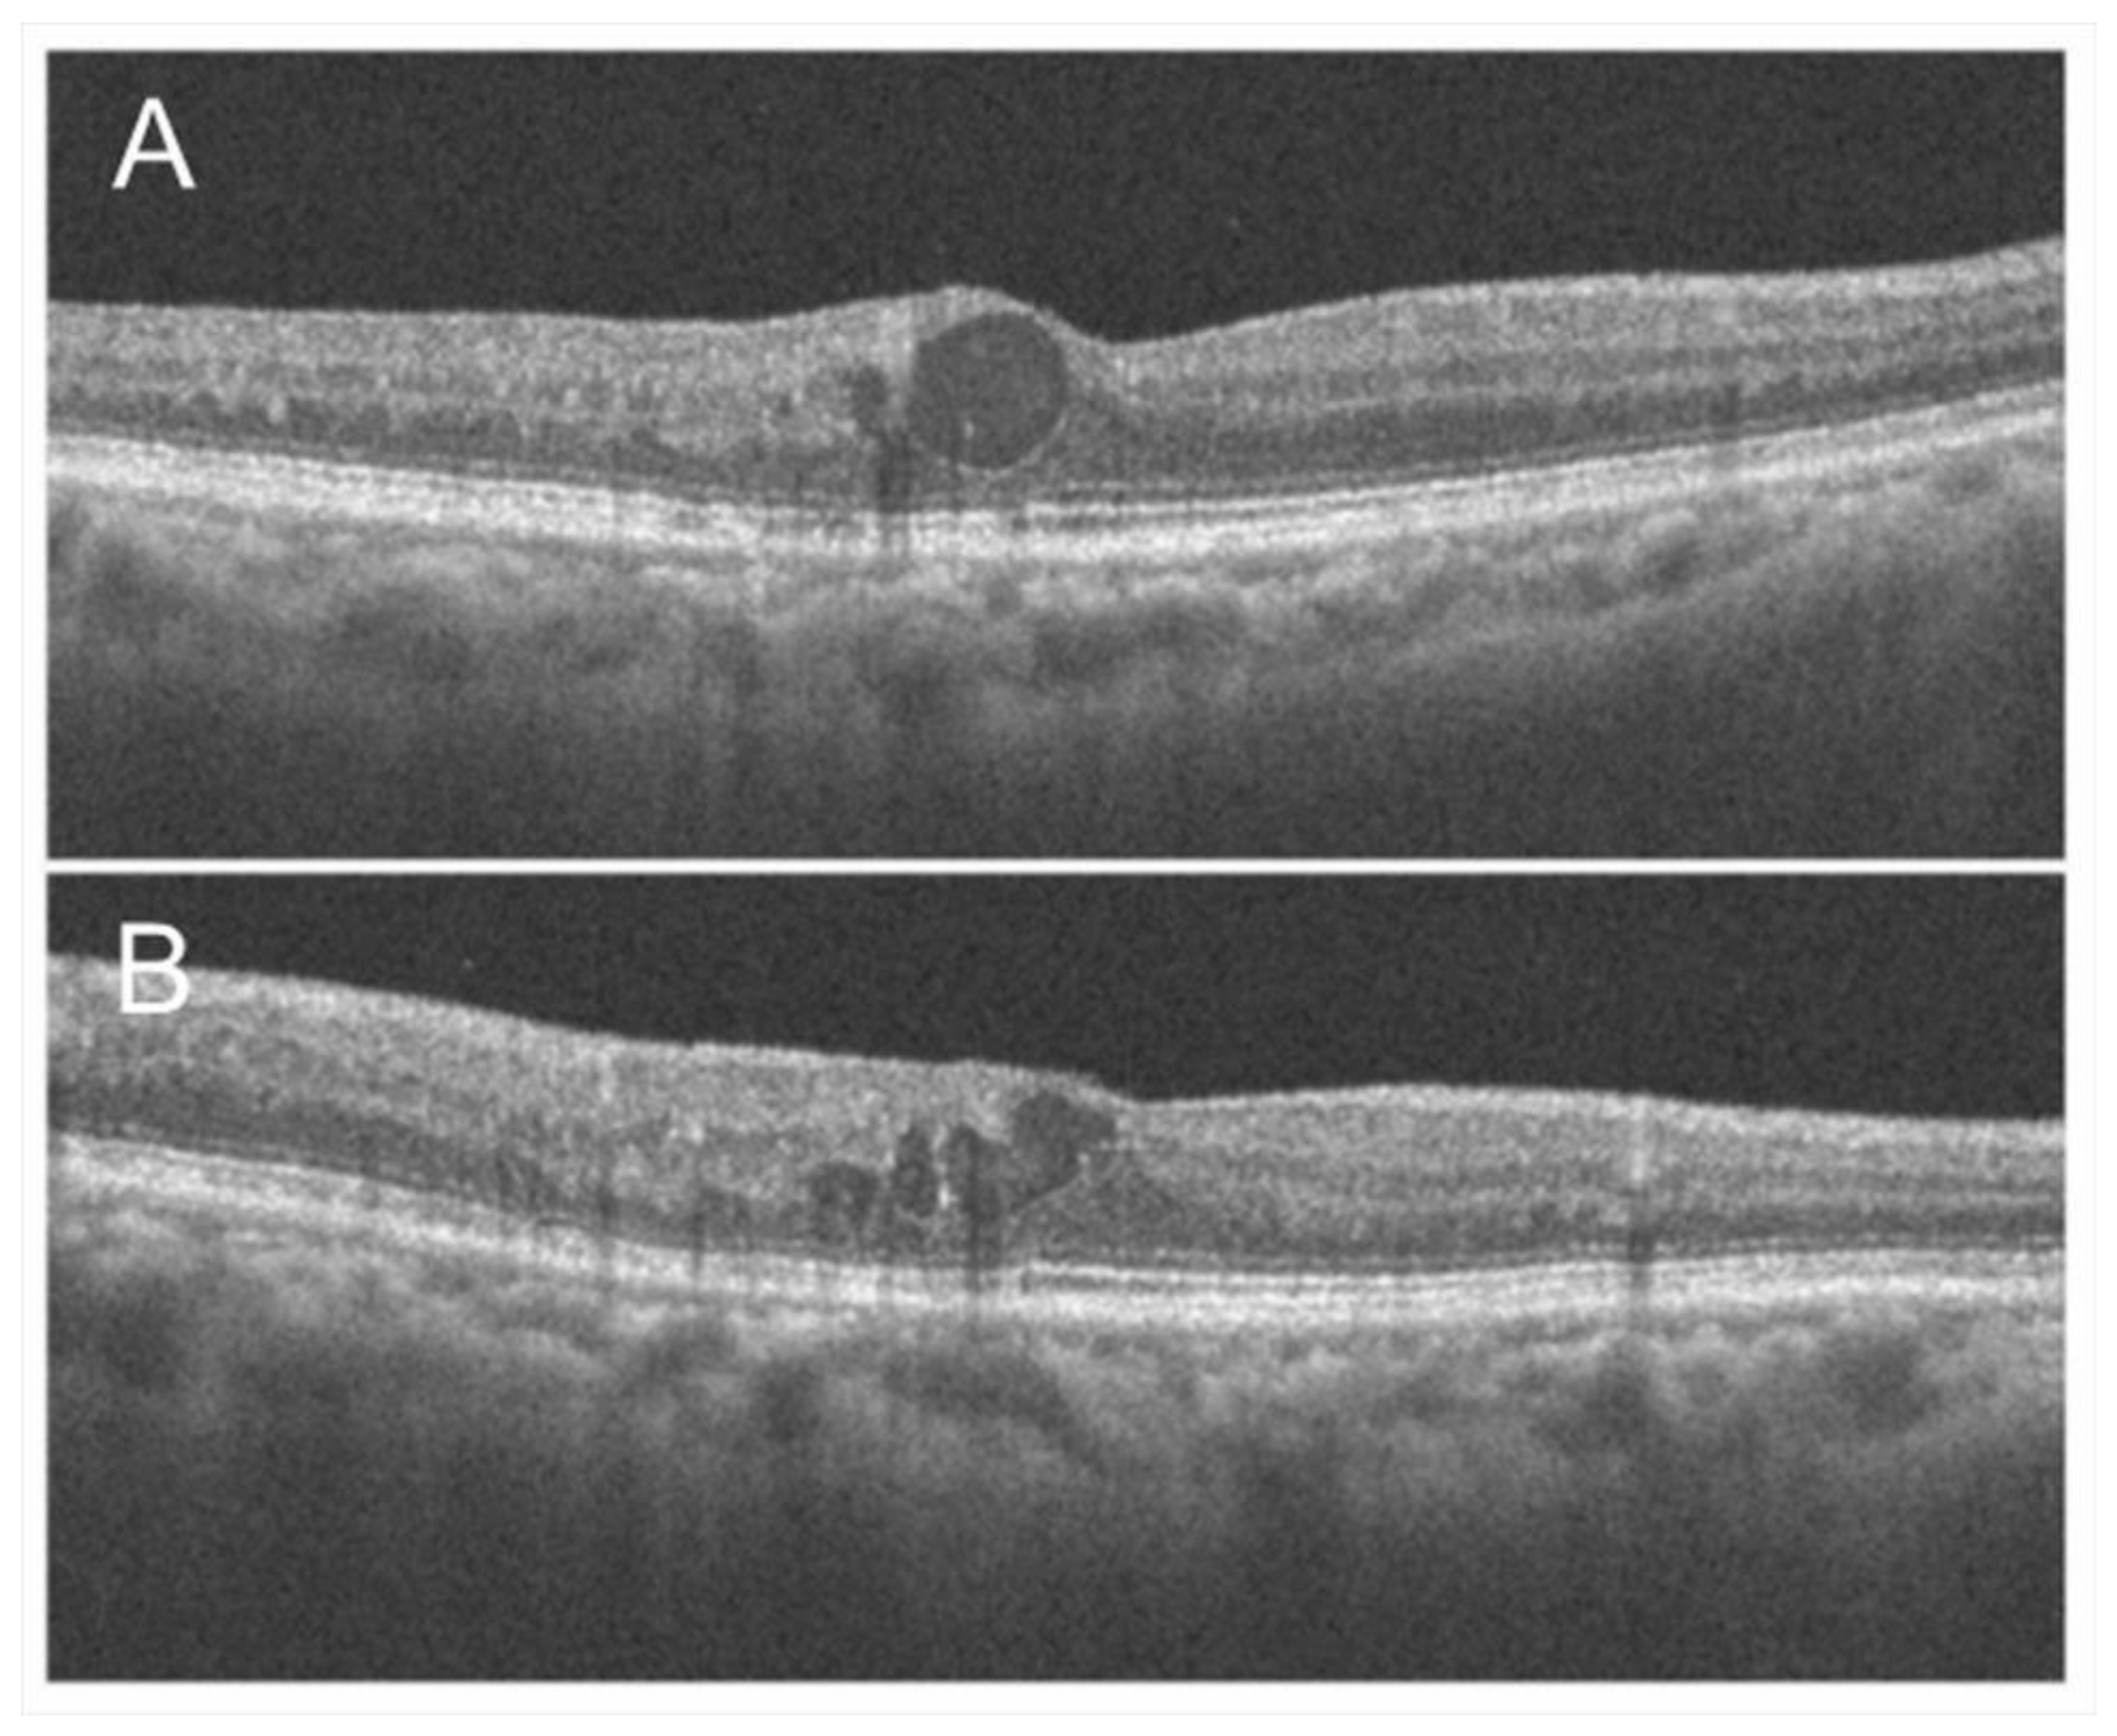

3.3. Macular Edema

- Hasegawa, T.; Ueda, T.; Okamoto, M.; Ogata, N. Presence of foveal bulge in optical coherence tomographic images in eyes with macular edema associated with branch retinal vein occlusion. Am. J. Ophthalmol. 2014, 157, 390–396.e1. [Google Scholar] [CrossRef]

- Hasegawa, T.; Masuda, N.; Ogata, N. Highly reflective line in optical coherence tomography images of eyes with macular edema associated with branch retinal vein occlusion. Am. J. Ophthalmol. 2015, 159, 925–933.e1. [Google Scholar] [CrossRef]